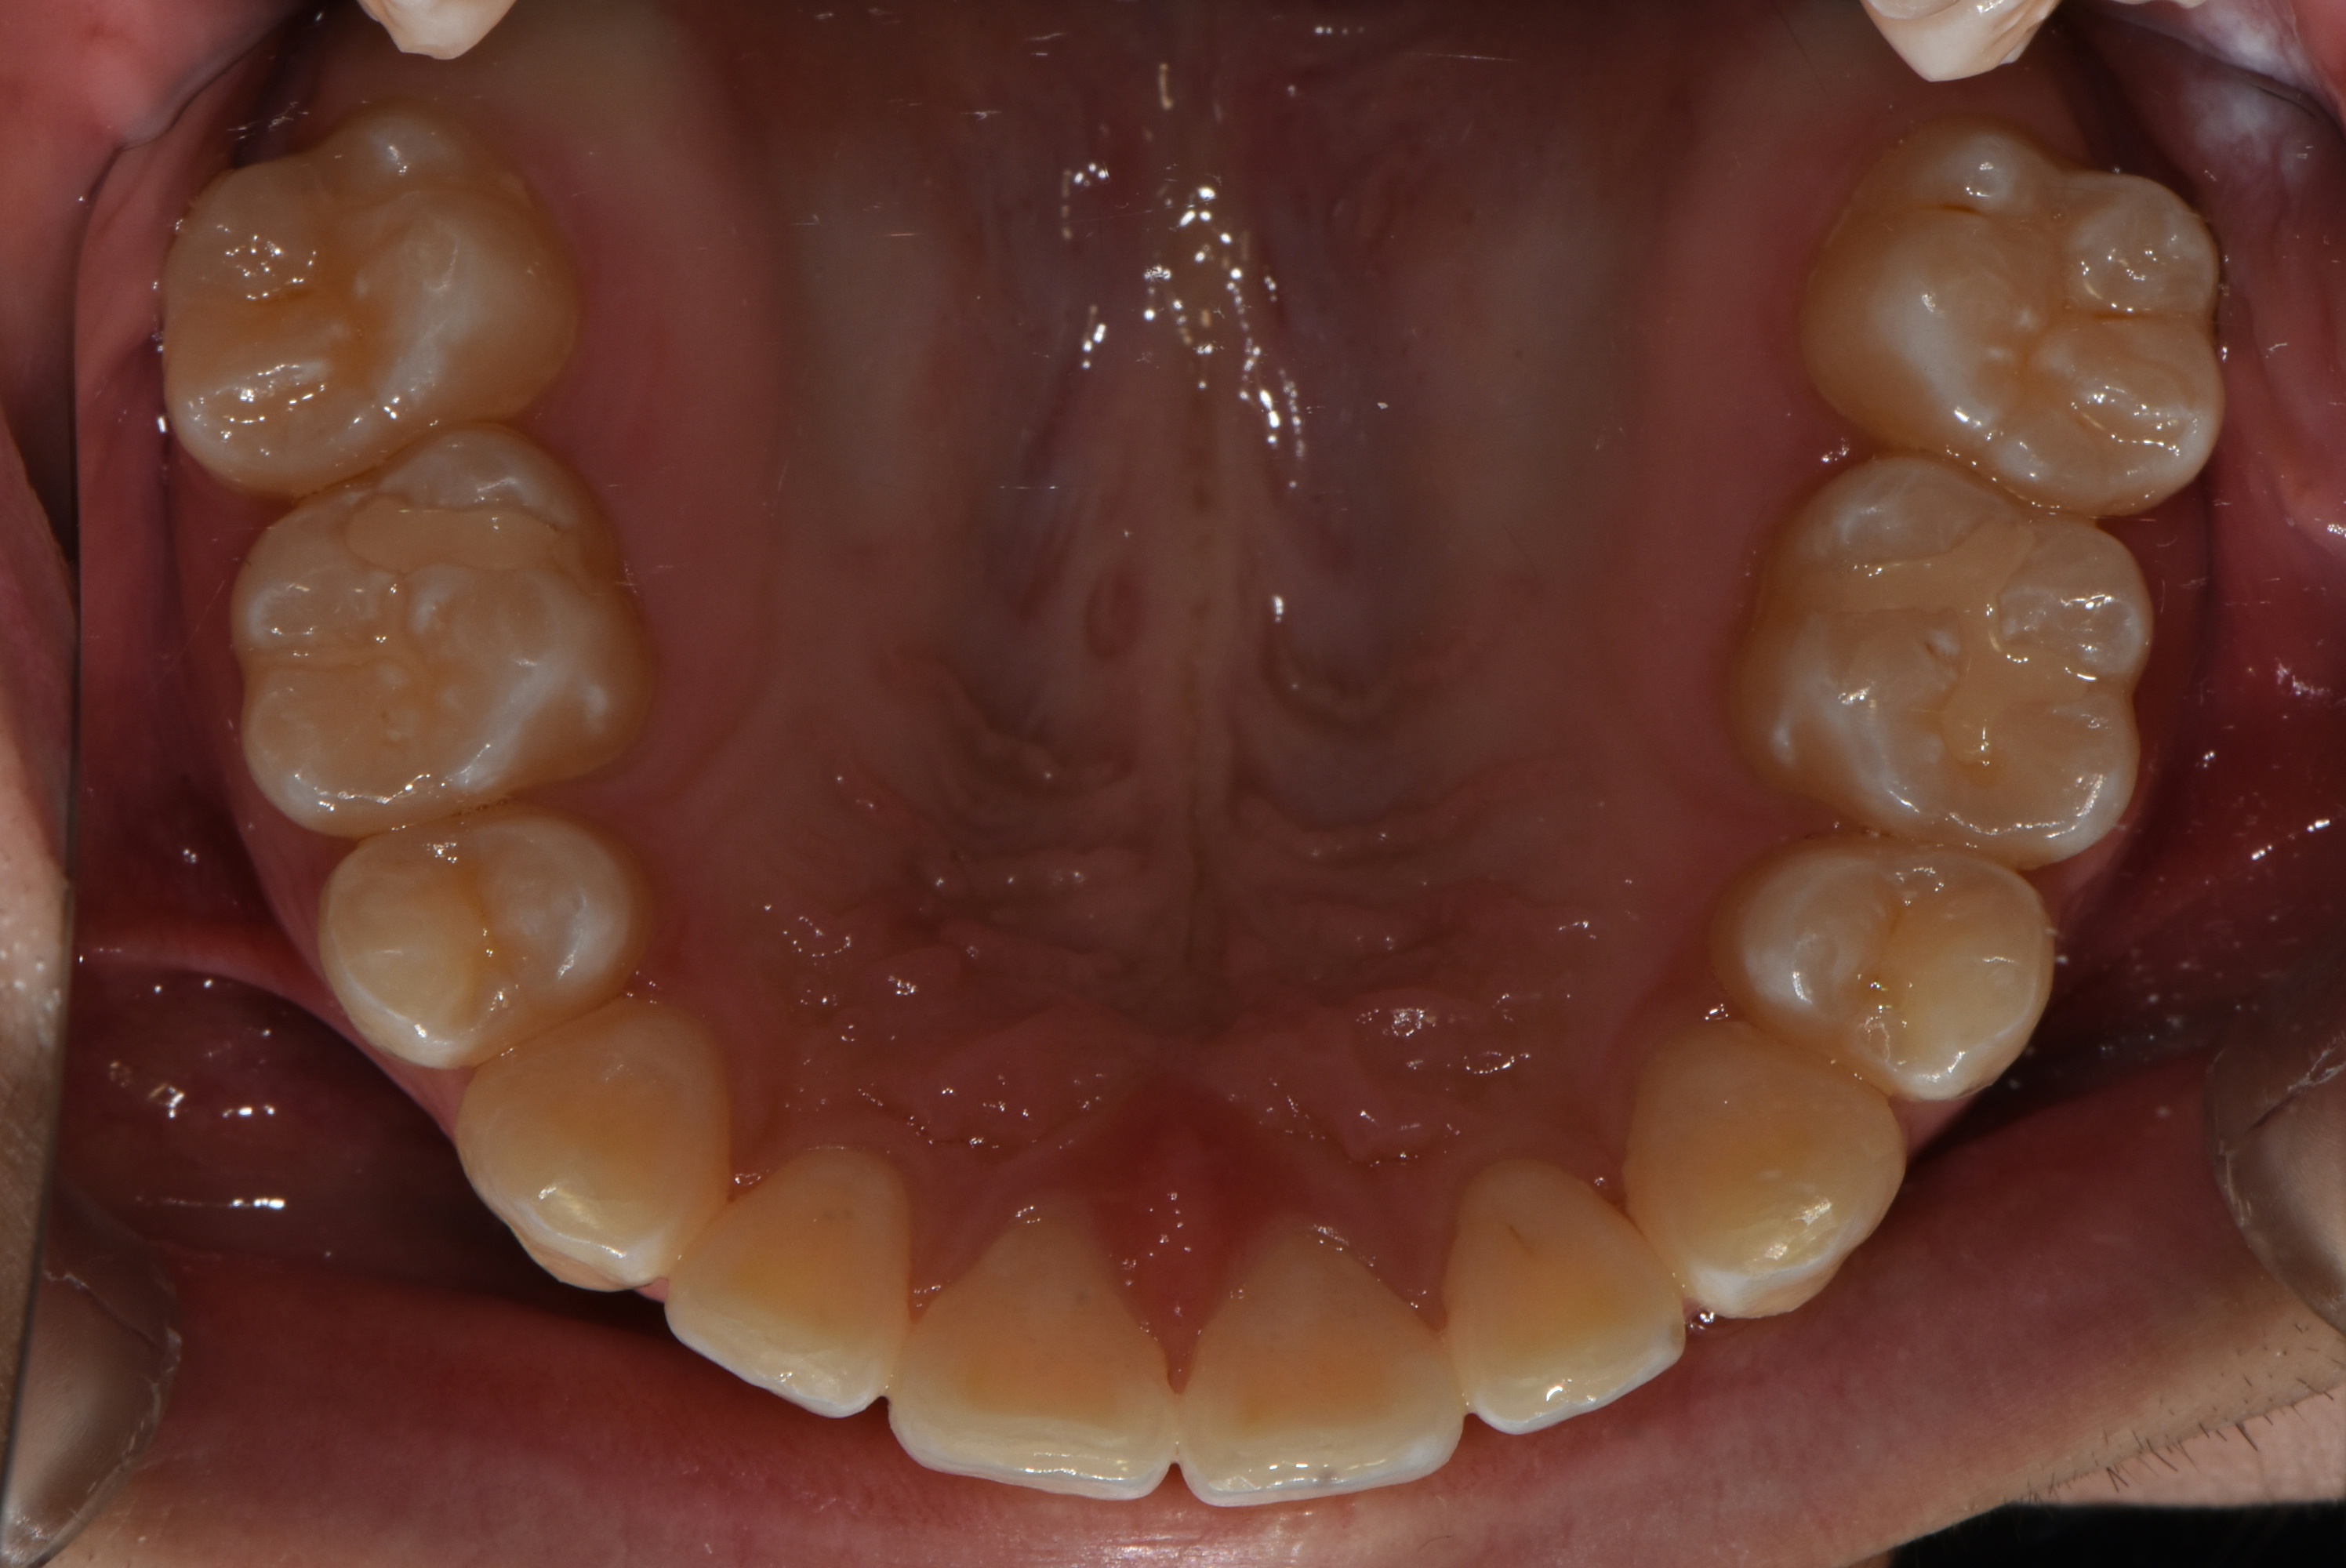

치료 전 사진입니다.